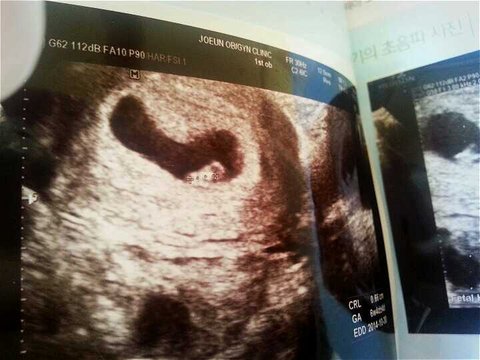

아기집밑에 까만집같은건뭔가요???

자세히 아기집바로밑에 아기집같이생긴까만거 저건뭘까요 집에와서보니 계속신경쓰이네요